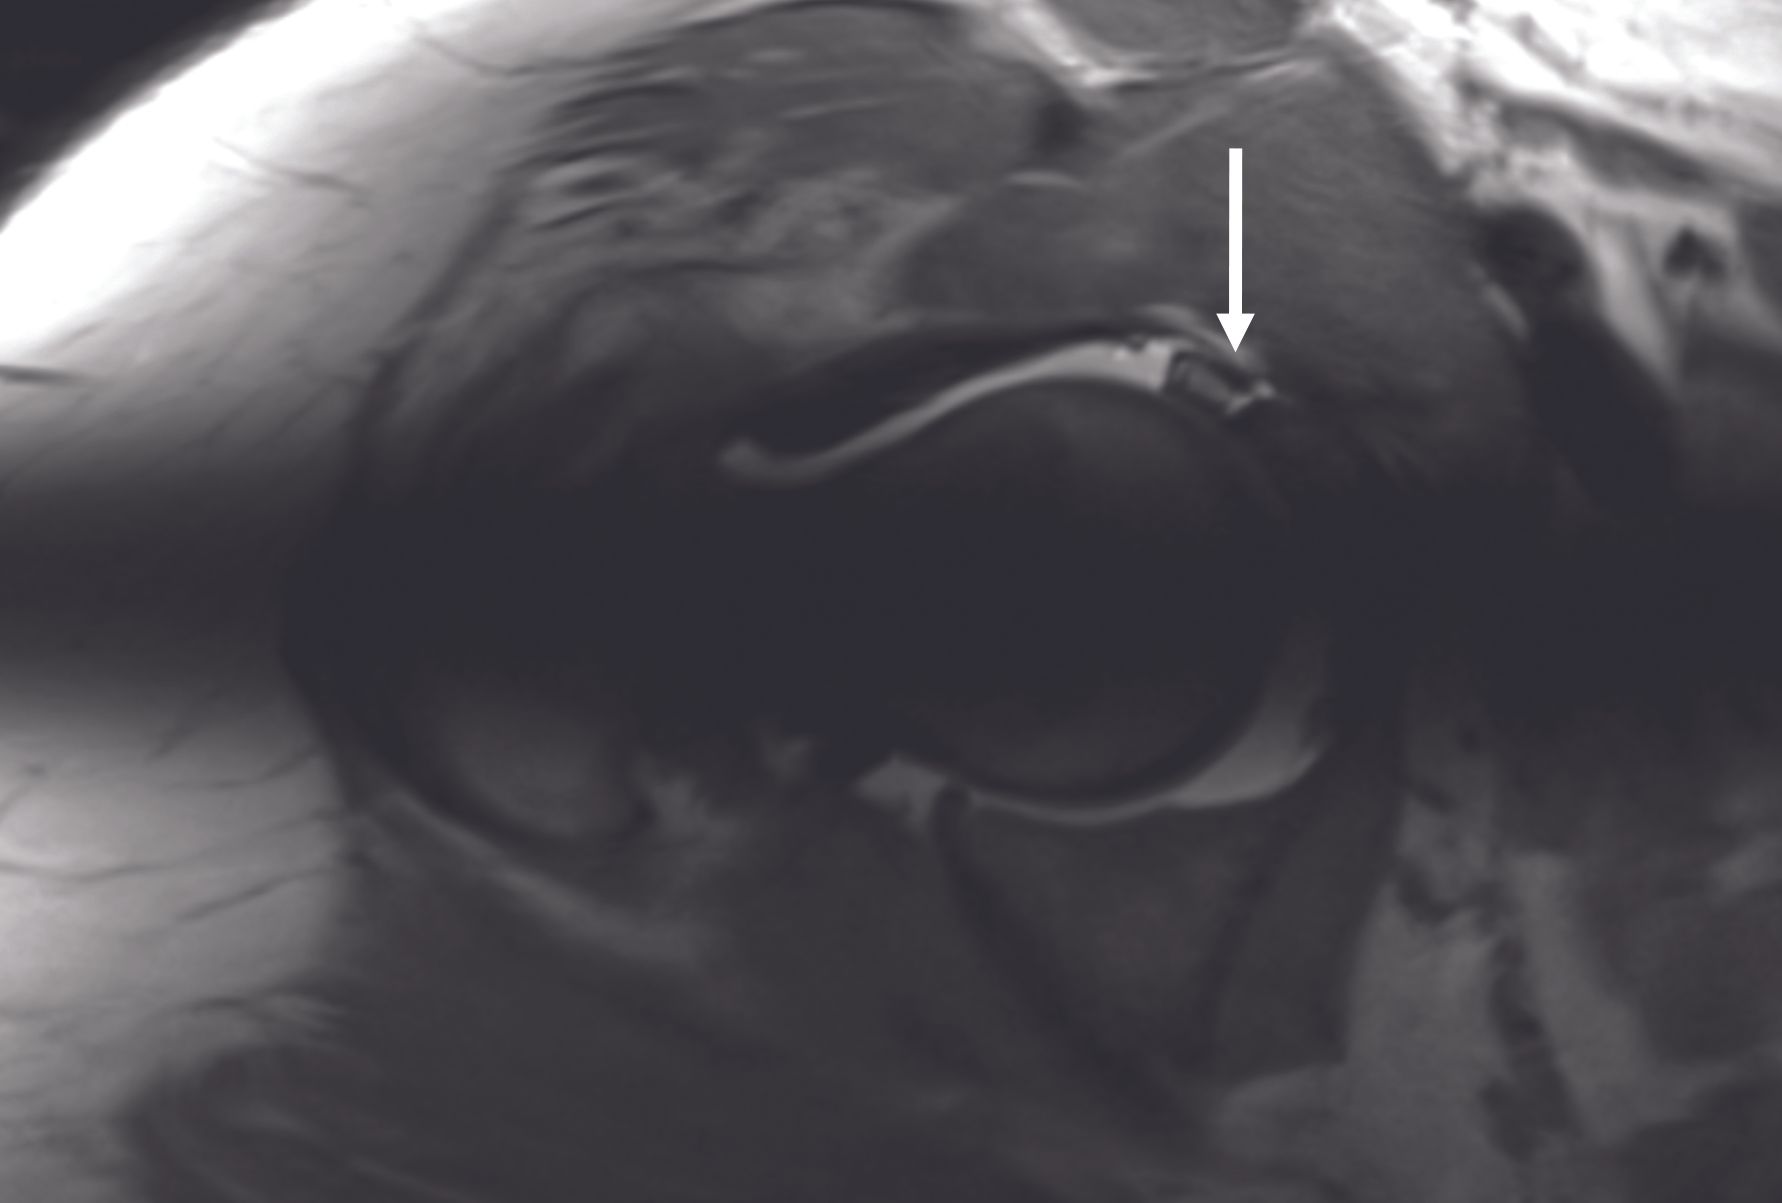

Finally, radiographs can exclude the presence of advanced arthritic changes, for which conservative hip surgery is no longer appropriate, and arthroplasty options should be considered. Arthro-MRI is the imaging procedure of choice for assessing the labrum and cartilage. Injection of contrast material into the hip joint allows better visualization of the labrum and cartilage. Lesions of the labrum (Figure 6) are most often found in the anterosuperior part of the joint. MRI with radial reconstructions allows better localization and quantification of the cam effect morphology (Figure 7). The alpha angle can also be measured on this imaging modality.

Femoro-acetabular impingement (FAI), described by Ganz in 2003 (1), is a frequent cause of hip joint pain in young adult athletes. Morphological alterations of the acetabulum (pincer effect), of the head-neck junction (cam effect), or femoral torsional deformities are the main causes of this dynamic impingement (Figure 1).